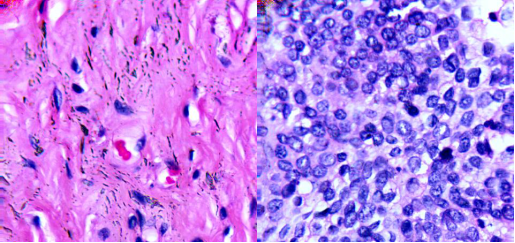

圖2 (a)100X宮頸癌非腫瘤切片 (b)100X宮頸癌腫瘤切片

圖3 左邊:40X膀胱癌非腫瘤切片;右邊:40X膀胱癌腫瘤切片